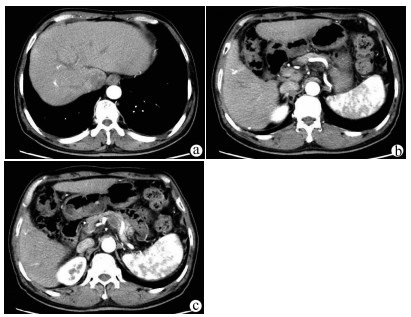

原发性肝淋巴瘤伴贫血和低蛋白血症1例报告

李伟锋, 吴帆

2021, 37(8): 1911-1913. DOI: 10.3969/j.issn.1001-5256.2021.08.034

摘要(953) HTML (226) PDF (2390KB)(51)

摘要: